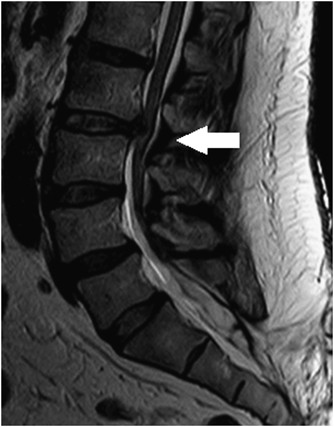

متخصص طب فيزيكي و توانبخشي -بيماري هاي عضلات،استخوان،مفاصل،اعصاب محيطي، ديسك وستون فقرات،ناهنجاریهای اسکلتی و گودی کمر وقوزپشتی وزانوی ضربدری وپرانتزی ،كمردرد وگردن درد،درد کتف وشانه ،صافی وگودی کف پا وتجویزکفی وکفش طبی ،سوزش وگزگز وداغی پاها ودستها،سردرد های مقاوم به درمان ،ورزش درماني وحركت درماني و تمرين درماني ،طب سوزني،دردهاي اسكلتي وعضلاني،درمان غير جراحي ديسك وستون فقرات ،نوار عصب وعضله،ليزر درماني وفيزيوتراپي،عمل بسته دیسک،اوزون درمانی